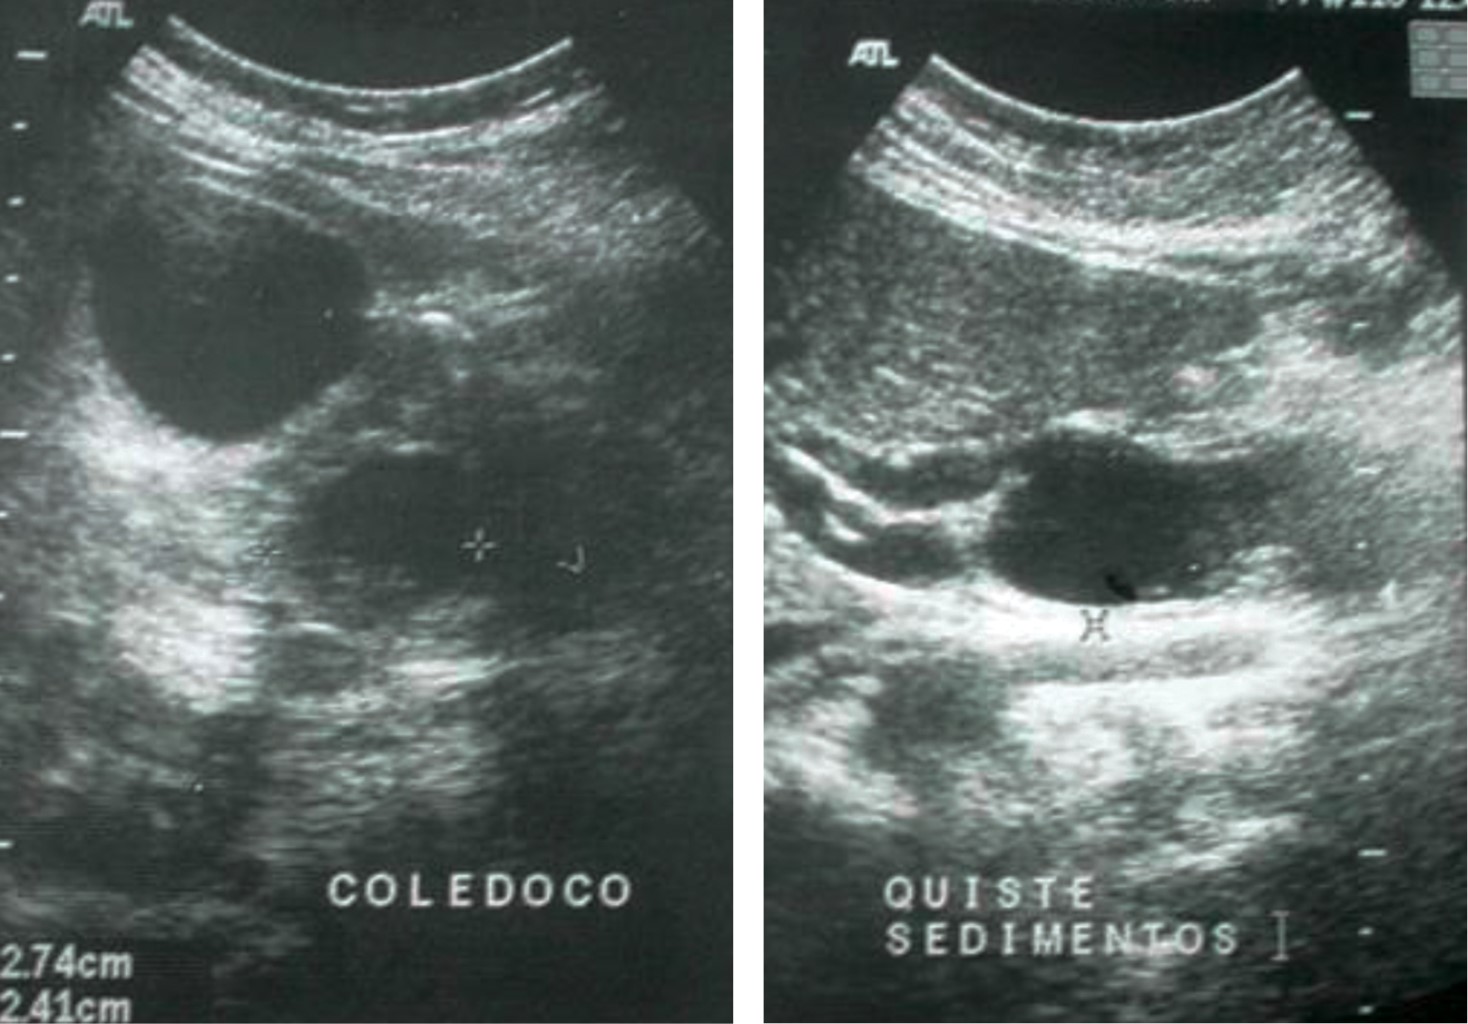

Un ultrasonographic study of liver and biliary tract showed normal liver, proximal common bile duct of 7 mm, dilated distal common bile duct of 27 mm with microliths inside, with an appearance suggesting a common bile duct cyst, gallbladder measuring 82 × 37 mm with a wall thickness of 2 mm without stones in its interior, and pancreas, kidneys, and spleen normal. The ultrasound diagnostic impression was that a common bile duct cyst with microliths inside (Figure 2).

Another ultrasonographic study was performed as an outpatient that showed a normal liver, an anechoic gallbladder measuring approximately 6.3 × 3.1 cm with a thickness wall of 4 mm, and the presence of a common bile duct cyst in the distal region measuring 1.35 × 2.4 × 0.72 cm (Figure 3). The common bile duct was of normal caliber in its proximal segment with well-delimited edges without significant compression of neighboring organs.